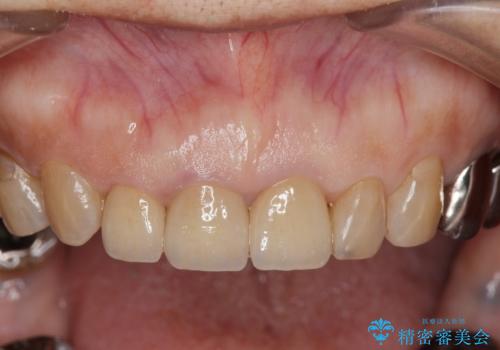

前歯の審美改善

- 孫娘の結婚式に合わせて前歯を綺麗にして写真映りをよくしたいと来院されました。

結婚式に合わせて根管治療からのやりかえを短期集中治療で計4回で終える計画を立てます。

- 40万円(仮歯・ファイバーコア・ジルコニアクラウン×3)費用は治療当時の料金となります

セラミック治療は外から見えるのはクラウンの色味・形態、歯肉の状態のみですが、X線撮影において現れるクラウンと歯牙の適合や、ファイバーコアの精度・根管充填の密度に、より長い予後を達成するための要素が含まれると考えます。